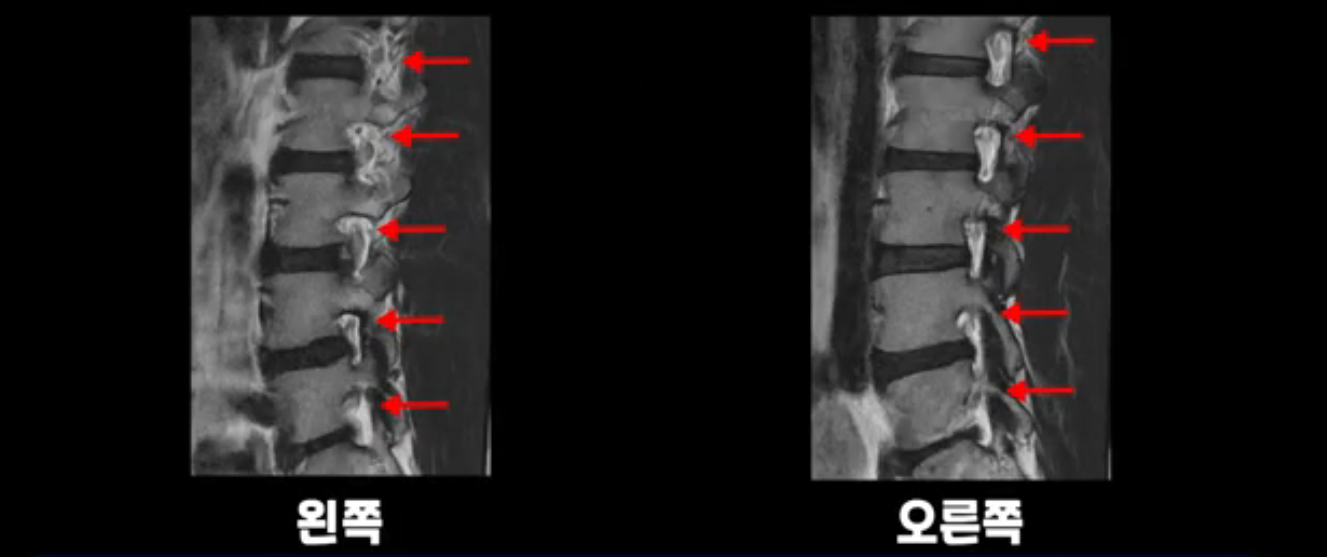

추간공도 보시다시피 왼쪽, 오른쪽 전부 다 매우 넓어서 신경이 눌릴만한 부분이 전혀 보이지 않습니다.

앞서 1번 2번, 4번 5번, 5번 1번의 디스크가 찢어지고 조금 밀려 나온 게 최근에 찢어진 게 아니고 오래된 걸로 보인다고 말씀 드렸죠. 왜 그럴까요? 만약 급성으로 찢어진 것이라면 아주 심한 디스크성 통증이 있겠죠. 기침이나 재채기를 하면 심하게 아프고 허리를 조금만 구부리거나 비틀면 아주 날카로운 통증들이 생길 겁니다. 그런데 이분은 이런 증상이 전혀 아닙니다. 또 디스크의 밀려나온 정도도 전혀 심하지 않기 때문에 이분이 가지고 계신 양쪽 다리 저림, 특히 이분은 누워있을 때도 양쪽 발이 발가락까지 쑤신다고 하는데 이정도 디스크 때문에 그런 증상은 생길 수가 없는 겁니다. 이처럼 이분의 가벼운 디스크 탈출은 이미 오래 전에 진행되었고 섬유륜 자체는 이미 아문 상태인데도 디스크내장증을 진단받은 환자들 중에는 본인이 섬유륜 파열 환자라고 끝까지 믿는 분들이 많습니다. 다시 말하지만 디스크내장증이라는 진단을 받은 환자들을 보면 거의 전부 다 섬유륜 파열 증상이 아닙니다. 증상이 완전히 다릅니다. 진단이 애초에 잘못되면 어떤 치료를 받아도 좋아질 수 없습니다.

이 HIZ는 섬유륜이 찢어졌다가 이미 아문 뒤에도 얼마든지 보일 수 있는 흔적일 가능성이 있어서 재채기를 하면 아픈지, 허리를 구부릴 때 날카로운 통증이 생기는가 등의 증상으로 구별해야 하는데 MRI만 보고 HIZ가 보이면 그게 마치 통증의 원인인 것처럼 얘기하는 의사들이 있습니다. 이분 MRI를 자세히 보고 증상을 정말 자세히 들어본 의사가 있었더라면 다른 환자분들처럼 증상과 MRI가 일치하지 않는다는 얘기를 들을 수 있었을 텐데 이분은 그런 얘기는 듣지 못했습니다.